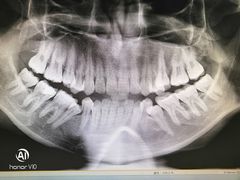

• 岳辰齿科(浦东长泰店)

• -岳辰齿科(浦东长泰店)